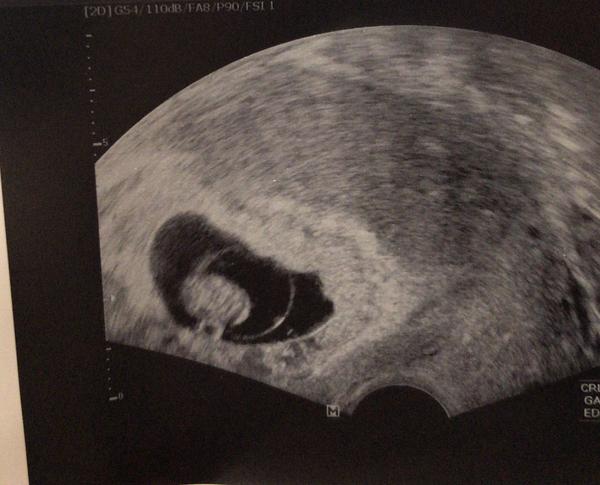

Moc prosím o útěchu - jsem tehu a máme z toho velkou radost. Ale jelikož jsem o první mimi prisla, (pak úspěšně porodila), tak se strašně bojím, aby se to nestalo znovu.. jsem 7+2, na kontrole jsem byla 16.10. a už tlouklo srdíčko, ale mimi bylo tak strašně malinke, ze jsem neviděla nic jiného, než srdíčko. Paní dr říkala, ze velikostne odpovídá -2dny, což by mělo byt Ok.. Ale jde mi o to, ze u prvního také bylo tlukouci srdíčko a na příští kontrole už ne... 😢 Pak se povedlo a teď znovu, tak mám strach.. 😔 Na kontrolu jdu až po 14ti dnech.. to čekání a nevědomost je hrozná..